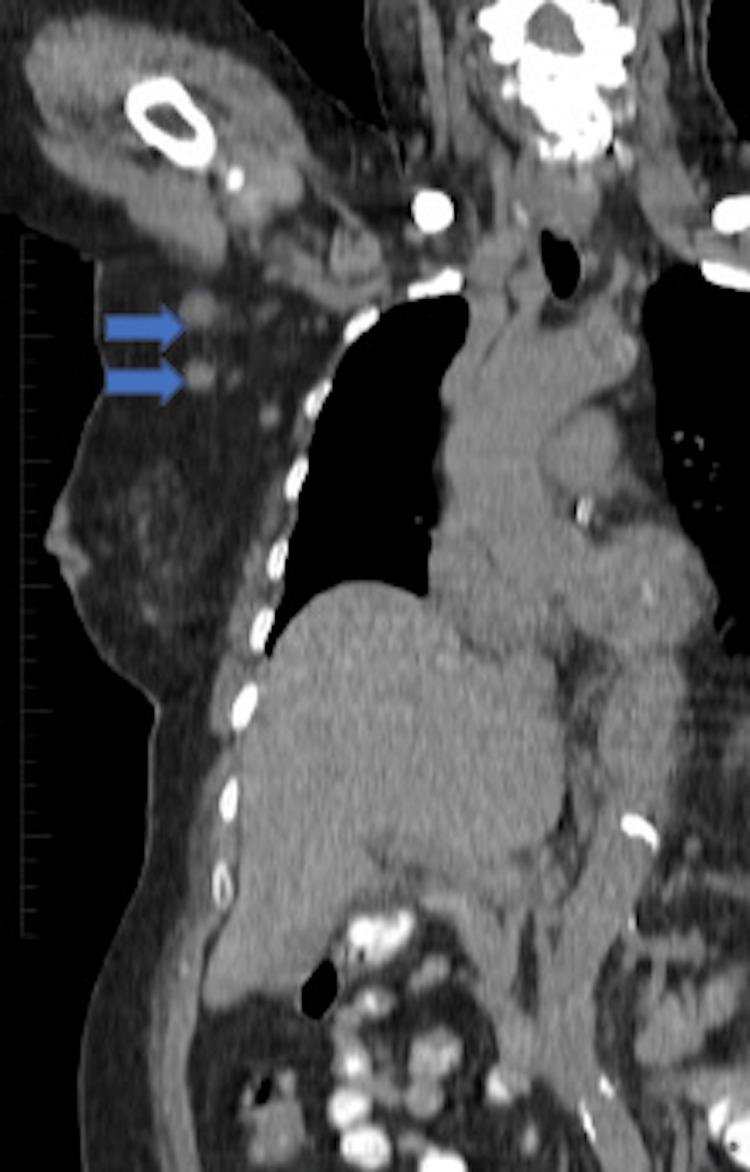

https://cdn.ncbi.nlm.nih.gov/pmc/blobs/4555/9392481/b121fc950a02/cureus-0014-00000027112-i01.jpg